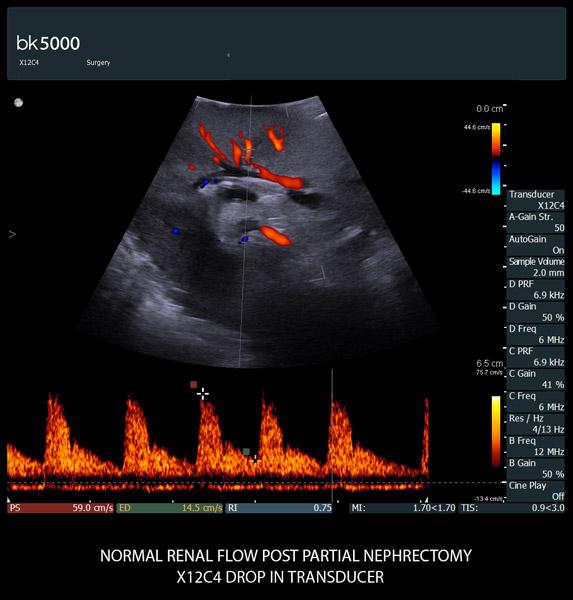

Extremely sensitive color Doppler with superb spatial resolution identifies arterial and venous blood supply to the tumor. This is especially important in procedures where selective clampingis needed. Unsurpassed 3D imaging enables easier identification of key anatomical landmarks and dissection planes.

The unique Drop-In transducer enables access and visualization of complex organs and difficult-to-access anatomy in real-time. For example, in kidney navigation and difficult-to-access endophytic and exophytic tumors, the small, compact, curved linear array Drop-In transducer enables a wider field of view for faster examinations. The specially-designed fin grasped by the robotic arm ensures maximum control and organ contact so you can get the information you need.